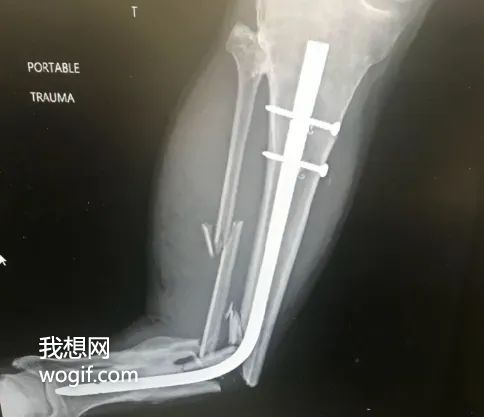

某病例x光:康復期間,再次車禍,鋼管都彎了(圖)

我想網(wǎng)》分享一個請選擇性觀看的圖片,康復期間,再次車禍,鋼管都彎了,一張看著都疼GIF圖,堪稱“折上折”,話說這個小腿折的,從人腿變成了豬腿,有專業(yè)人士么?這種該應該如何處理,感覺植入的物體不太容易取出了...